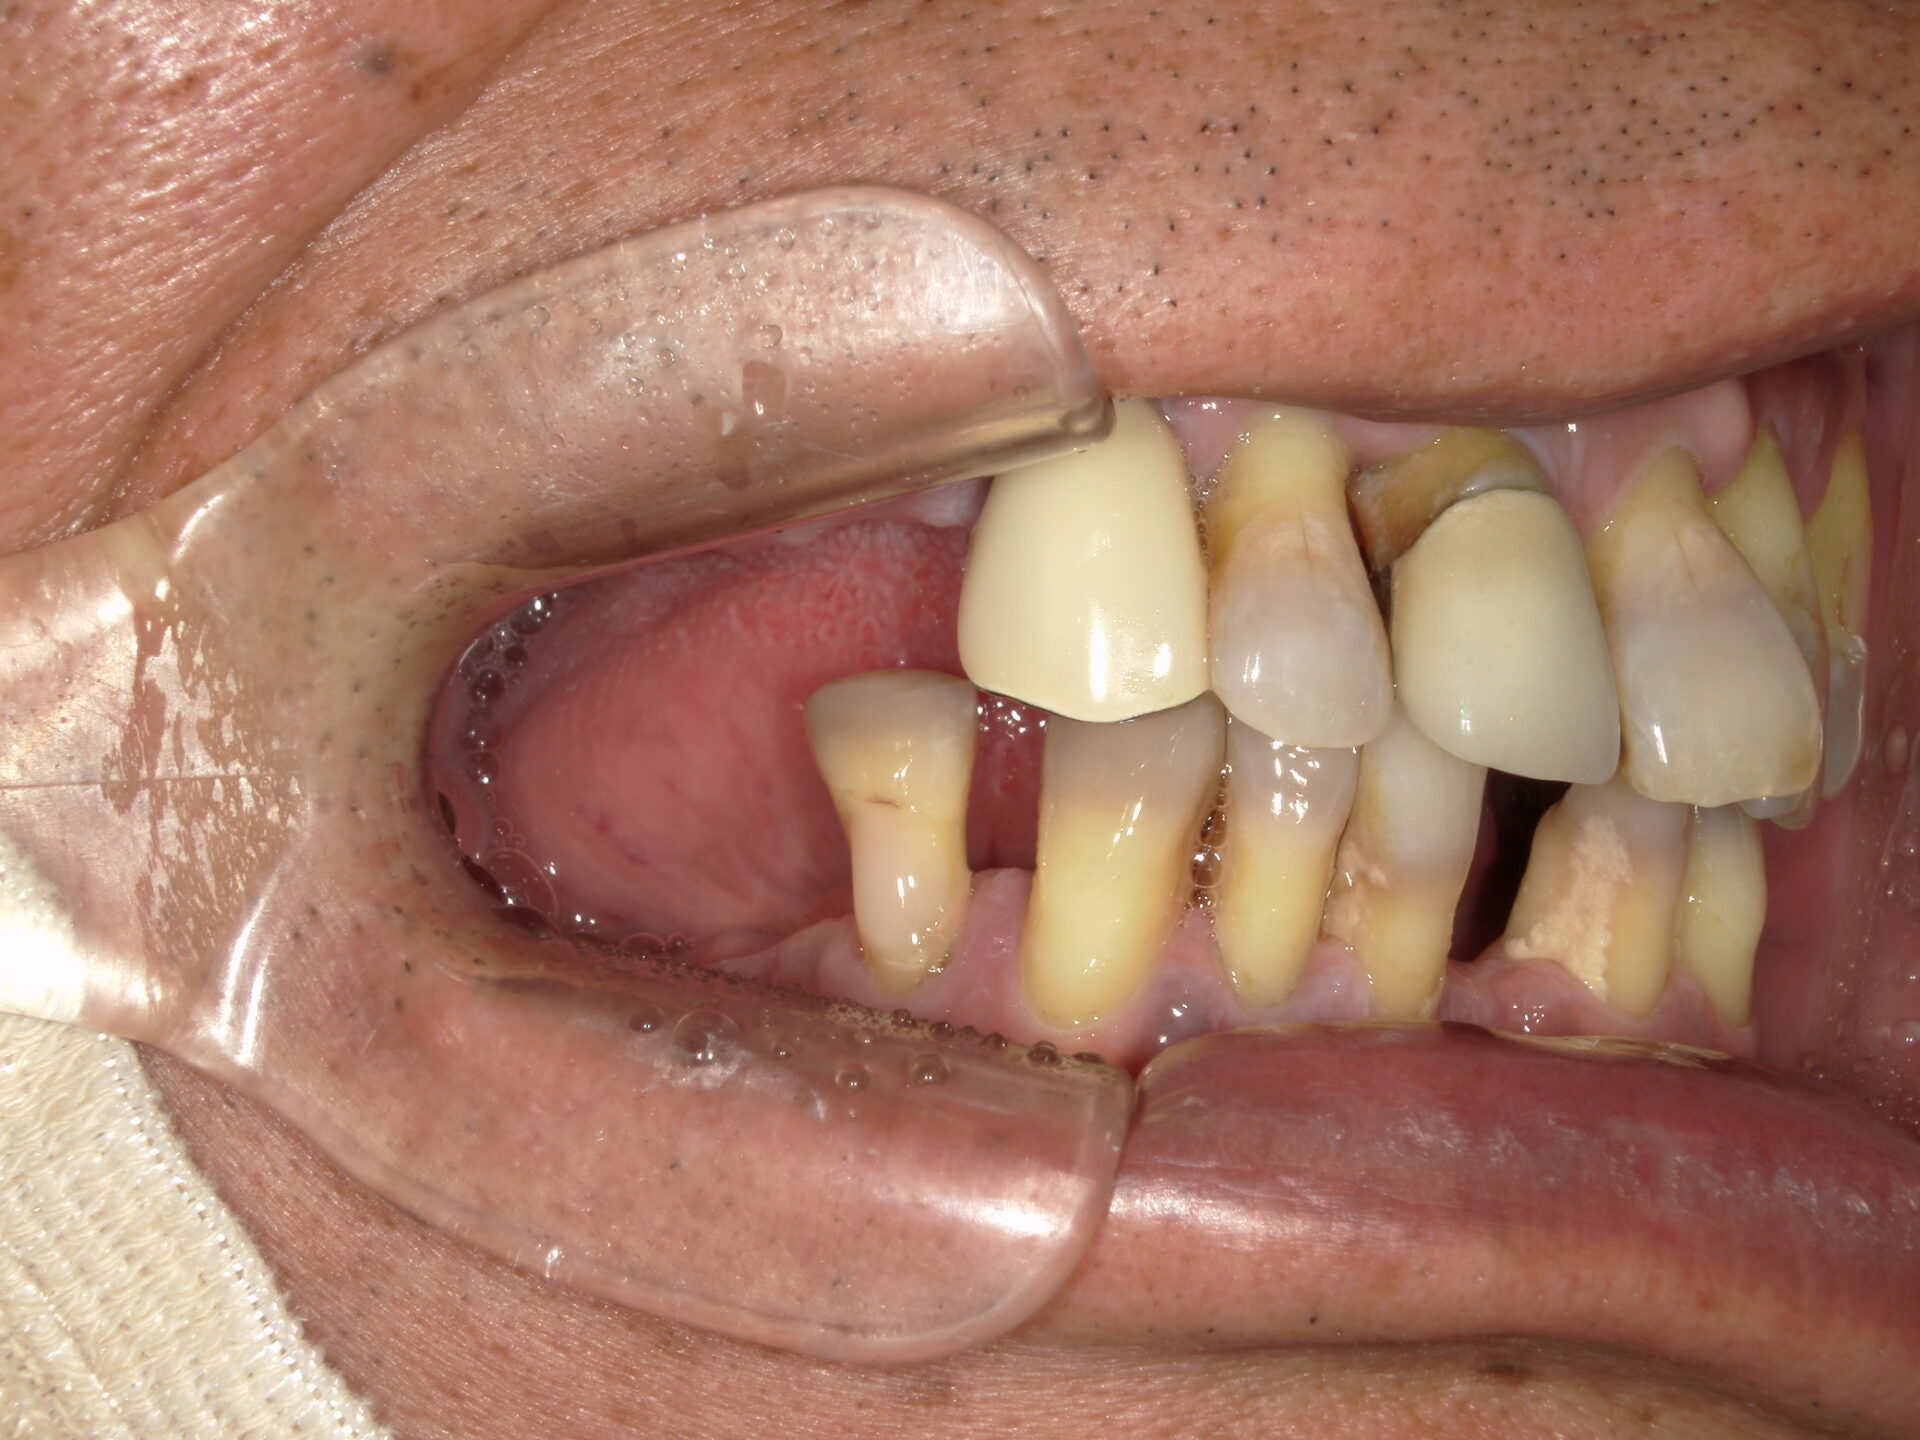

before

after

患者さんの年齢 50代 男性 症状 何も噛めない 治療内容 インプラント治療(オールオン4) 費用 費用900万(税抜) 治療期間・回数 治療期間2年・通院回数12回 メリット なんでも噛めるようになる 見た目が綺麗 デメリット・リスク 骨造成などで費用が増える場合がある - インプラント治療